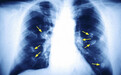

从光滑程度看,良性的结节外形是比较光滑的,并且边界清晰;恶性的结节表面粗糙,边界不清晰。从形状看,良性的肺结节通常是圆形或是椭圆形的;而恶性的结节很少有这两种形状,大多是葫芦状的。从长大的速度来看,良性的结节几个月或是几年可能变化都不是很大;恶性结节很可能会随着时间的变化而慢慢长大。从软硬程度来看,如果是质地较硬的结节通常就是良性的;而恶性结节不会完全钙化的,质地不是很硬。从外侵的迹象来看,良性的结节通常不会有外侵的情况发生,不影响周围的器官组织;恶性结节很大可能会入侵到周围的组织,影响到其它的组织。

肺部小结节不能说就是早期的肺癌,像炎症、结核等都可能会在肺部形成结节,所以它的诊断是各种各样的。但是我们不得不小心恶性的肺部结节,若是发生病变那很可能会形成肺癌。而且也不能说良性结节就是绝对的安全的,若是转为恶性的结节,也是很不利的。若是结节突然长大,或是性质发生了改变,一定要及时就医诊治,以免错过了最佳的治疗时间。